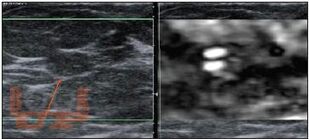

В книге освещены теоретические и клинические ключевые аспекты соноэластографического исследования, начиная от физических основ исследования и истории развития метода, до описания конкретных соноэластографических характеристик различных органов и тканей.

Учебно-методическое пособие рассчитано на ультразвуковых диагностов, гинекологов, хирургов и онкологов, специализирующихся на диагностике и лечении заболеваний молочной и щитовидной желез, органов брюшной полости и малого таза